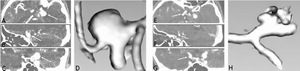

Association Between Vascular Anatomy and Posterior Communicating Artery Aneurysms

Publication: World Neurosurg. 2015 Nov;84(5):1251-5. PMID: 26074436 Authors: Can A, Ho AL, Emmer BJ, Dammers R, Dirven CM, Du R. Institution: Department of Neurosurgery, Brigham and Women's Hospital, Harvard Medical School, Boston, MA, USA. Background/Purpose: Hemodynamic stress, conditioned by the geometry and morphology of the vessel trees, plays an important role in the formation of intracranial aneurysms. The aim of this study was to identify image-based location-specific morphologic parameters that are associated with posterior communicating artery (PCoA) aneurysms. Methods: Morphologic parameters obtained from computed tomography angiography of 56 patients with PCoA aneurysms and 23 control patients were evaluated with 3D Slicer, an open-source image analysis software, to generate 3-dimensional models of the aneurysms and surrounding vasculature. Segment lengths, diameters, and vessel-to-vessel angles were examined. To control for genetic and clinical risk factors, the unaffected contralateral side of patients with unilateral PCoA aneurysms was used as a control group for internal carotid artery (ICA)-related parameters. A separate control group with visible PCoAs and aneurysms elsewhere was used as a control group for PCoA-related parameters. Results: Internal carotid artery-related parameters were not statistically different between the PCoA aneurysm and control groups. Univariate and multivariate subgroup analysis for patients with visualized PCoAs demonstrated that a larger PCoA diameter was significantly associated with the presence of a PCoA aneurysm (odds ratio = 12.1, 95% confidence interval = 1.3-17.1, P = 0.04) after adjusting for other morphologic parameters. Conclusions: Larger PCoA diameters are associated with the presence of PCoA aneurysms. These parameters may provide objective metrics to assess aneurysm formation and growth risk stratification in high-risk patients. |

Seeing More by Showing Less: Orientation-Dependent Transparency Rendering for Fiber Tractography Visualization